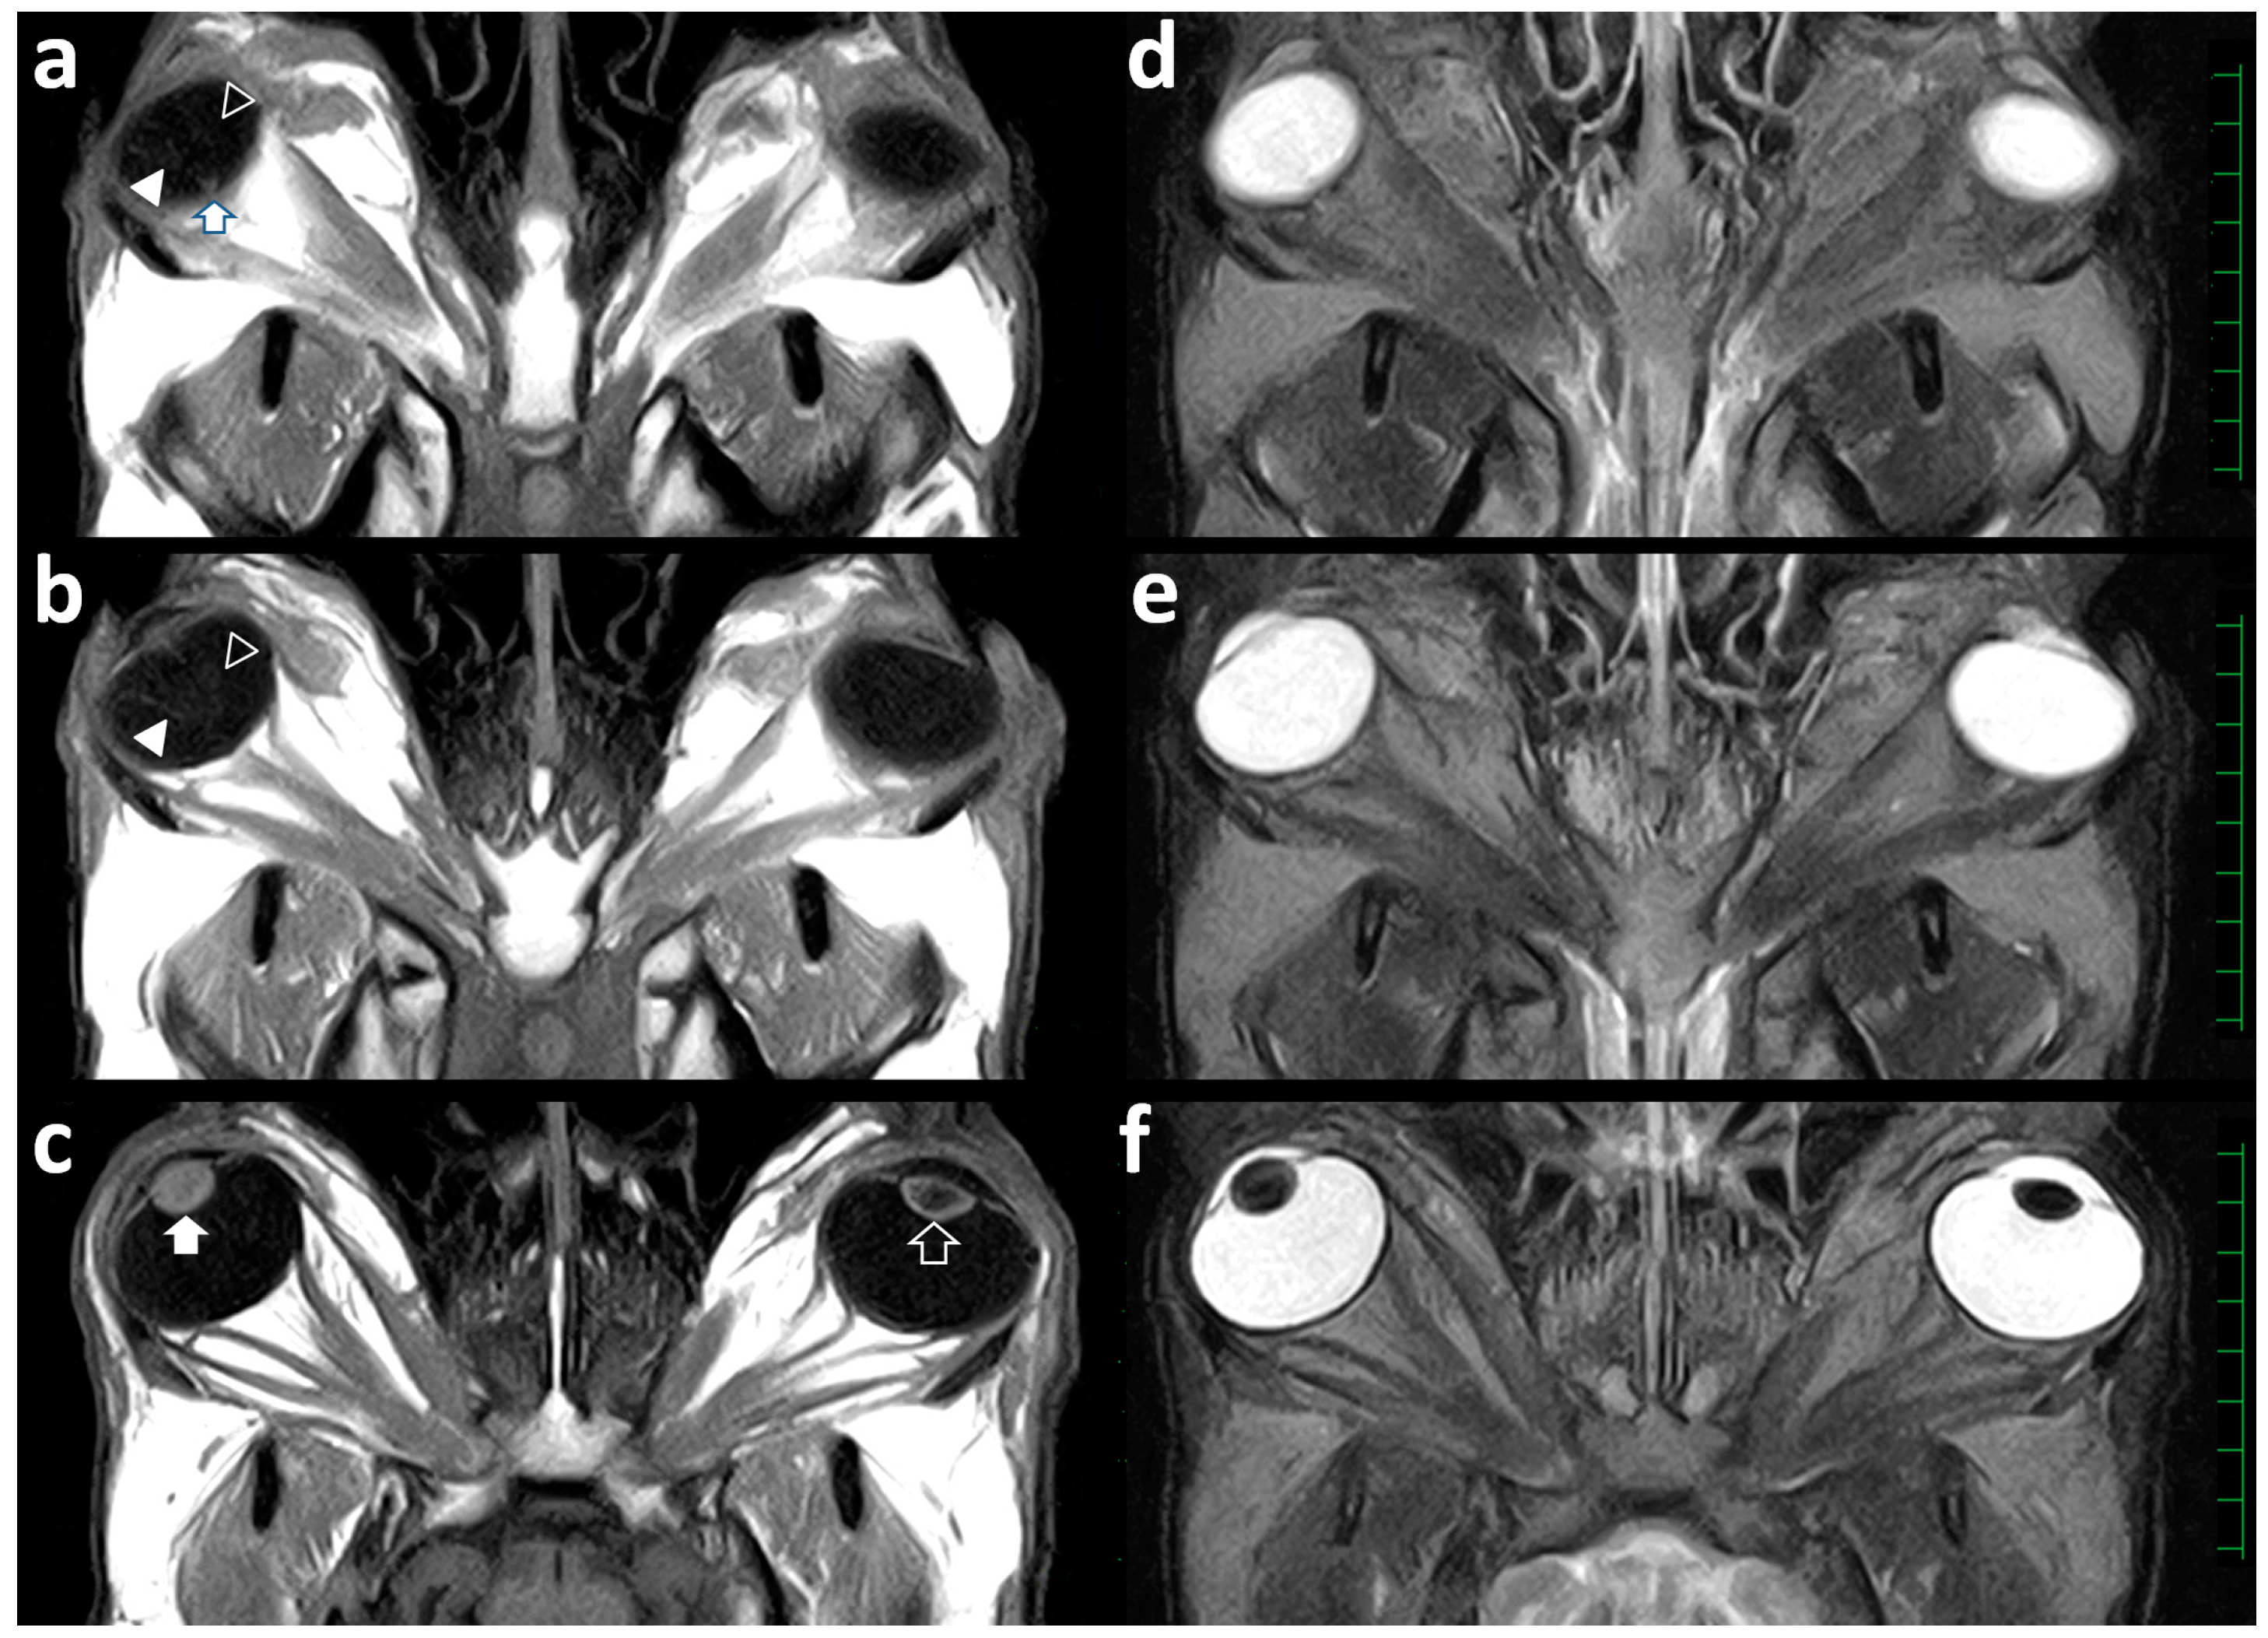

This case was euthanized one day after the examination according to the owner’s strong request because this case showed a moribund condition. At that time, MRI postmortem examination was conducted for the skull that was obtained at necropsy using a low-field scanner (AIRIS Vento 0.3 T, Hitachi Medical Corporation, Tokyo, Japan) and a human knee coil. T1-weighted (time of repetition (TR), 450; time of echo (TE), 21; slice thickness, 5 mm), T2-weighted (TR, 3224; TE, 100; slice thickness, 5 mm), and fluid-attenuated inversion recovery (FLAIR; TR, 11,000; TE, 100; slice thickness, 5 mm) images were acquired. In the dorsal section of the left eye on the T1-weighted, T2-weighted, and FLAIR images, the corn-like structure could not be observed within the vitreous body (Figure 3).

Figure 3.

Dorsal T1-weighted (a–c) and T2-weighted (d–f) views of the skull demonstrating the left and right eyeballs. (a) A V-shaped structure (empty and filled arrowheads) is seen within the vitreous body of the right eyeball. The tip of the V-shaped structure ends in the area of the optic nerve (arrow). (b) Two cystic structures are slightly evident in the center of one line of the V-shaped structure (empty arrowhead), despite no cystic structure being evident in another line (filled arrowhead) within the vitreous body of the right eyeball. A corn-like structure is not evident within the vitreous body of the left eyeball. (c) The right lens (filled arrow) is a spherical structure appearing entirely by a high signal intensity. The left lens (empty arrow) is normally visualized as a low signal intensity’s center surrounded by a high signal intensity’s line of the anterior and posterior lens structures. (d–f) Abnormal membranous structures are not evident within the vitreous bodies of the left and right eyeballs. The right lens is enlarged in the anteroposterior direction. Scale = 10 mm.

Intraocular structures such as the lens, the ciliary body, and the anterior chamber were not abnormal in the left eye. The dorsal sections of the right eye on the T1-weighted (Figure 3a,b) and FLAIR images revealed a V-shaped line within the vitreous body. The tip of the V-shaped structure was located at the beginning of the optic nerve. The medial line of the V-shaped structure was irregularly thickened at the center (Figure 3b). On the T1-weighted dorsal section of the right eye (Figure 3c), the lens appeared heterogeneously as a high signal intensity and was slightly thicker in the anteroposterior direction compared with that of the left eye. On the T1-weighted images, it was not possible to differentiate the border between the inner content of the lens and the anterior and posterior lens capsules. The lens in the right eye was heterogeneously seen as a low signal intensity on the T2-weighted (Figure 3f) and FLAIR images. There was no abnormality of the optic nerve, the extraocular muscles, or the fat tissues within the retrobulbar regions of both orbits. Additionally, there was no abnormality in the brain structures.